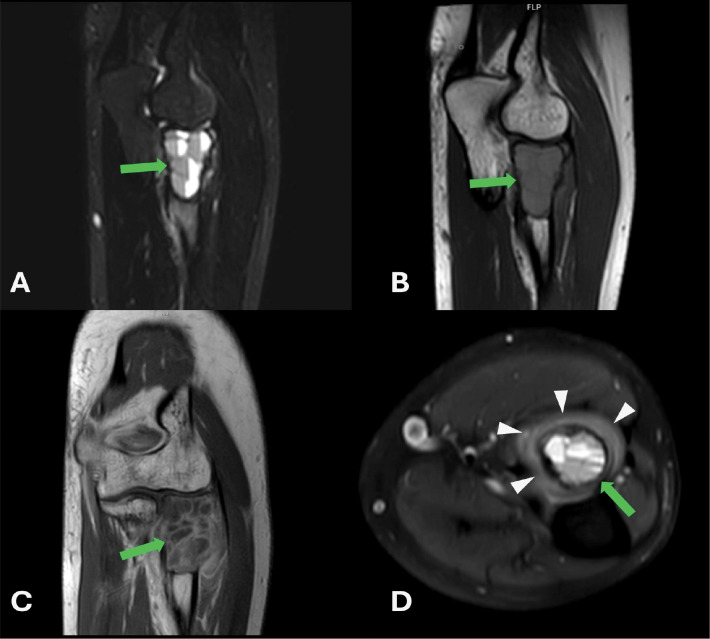

30岁男性左肘疼痛肿胀。多模态放射学评估显示一个扩张性溶解性骨病变,伴有液体-液体水平和周围软组织水肿,局限于桡骨头。组织学检查证实了动脉瘤性骨囊肿(SVABC)的实变,这是一种解剖学上罕见的病变。病变经过刮除处理,导致完全的临床解决。教学要点:结合影像学和组织学发现,准确诊断和有效治疗SVABC,特别是当发生在非典型部位时,它们可能模仿更侵袭性的肿瘤。

A 30-year-old male presented with pain and swelling in the left elbow. Multimodal radiologic evaluation revealed an expansile, lytic bone lesion with fluid-fluid levels and surrounding soft tissue edema, localized in the radial head. Histological examination confirmed the diagnosis of a solid variant of aneurysmal bone cyst (SVABC), an anatomically rare site for such lesions. The lesion was managed with curettage, leading to complete clinical resolution. Teaching point: integrating radiologic and histologic findings to an accurate diagnosis and effective management of SVABC, especially when occurring in atypical locations where they may mimic more aggressive neoplasms.